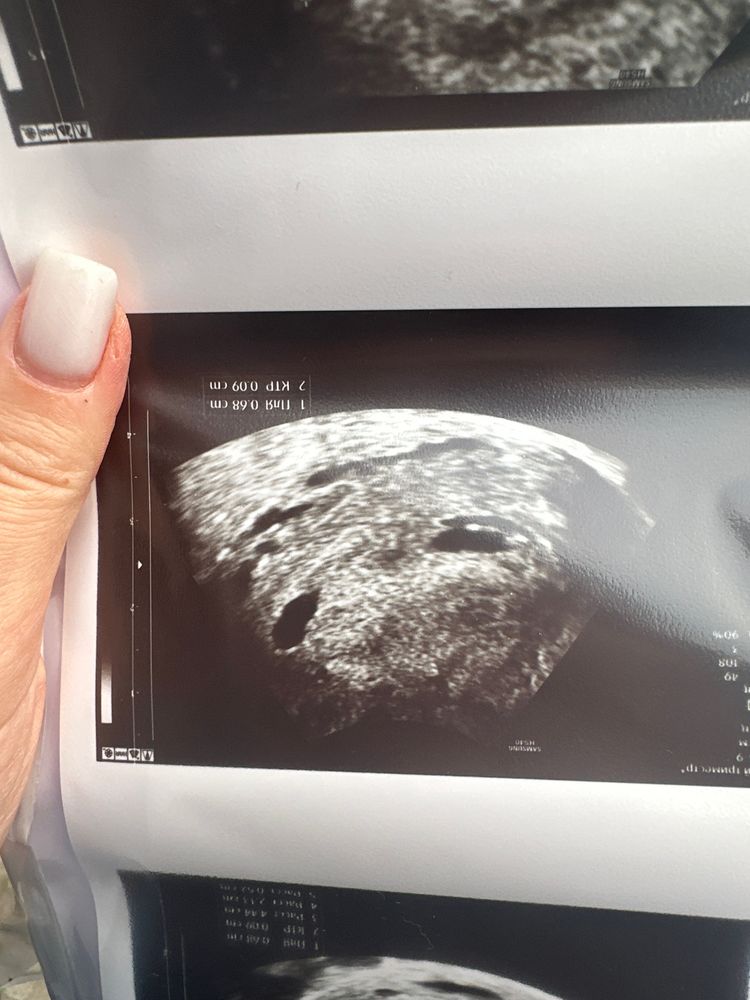

Сходила на второе узи к другому узисту,тоже не понимает,что происходит,в заключении про плодное яйцо вообще ничего не пишет,говорит,что скорее всего не развивающаяся,потом говорит про возможность двойни😣ох уж эта неопределенность(Говорит,я могу предположить,что это начало развития эмбриона(на фото ниже),но это прямо совсем сомнительно,сказала😣

Она на всех снимках замерила ктр как бы))) значит, есть жм, есть уже даже эмбриончик, просто маленький совсем. На первом снимке не пойман жм, но четко виден эмбрион.